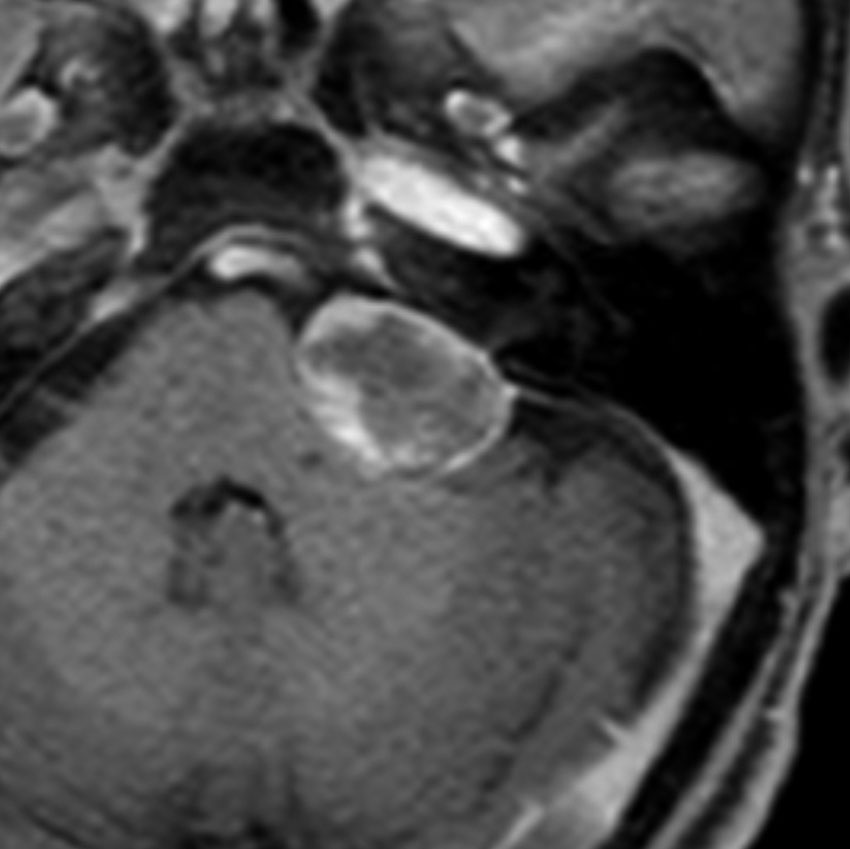

脳幹部の海綿状血管腫を手術するとき

左上のT2*でみられるように多発性海綿状血管腫の成人男性に発生した中脳海綿状血管腫です。複視と歩行失調で発症して,数回の脳幹部出血を繰り返し,水頭症になったために第3脳室開窓術がなされました。それでも出血は止まらず、両側の動眼神経麻痺による両側眼瞼下垂,歩行失調,嚥下障害などさまざまな中脳症状が進行しました。

しかたがないので手術で摘出しました。なんとか眼瞼が持ち上がるようになり歩行も可能で嚥下もできます。幸いだったのは感覚路(脊髄視床路)の障害による体性疼痛が生じなかったことです。

手術は経テント法 OTA という手法でした(クリックと手技が書いてあります)

片方の下丘の損傷だけでは神経脱落症状が出ないので,中脳内部の腫瘍を摘出するには下丘という狭い場所を切開して入りますが,この患者さんは左上丘も出血のために破壊されていて,間口が広かったといえます。でもこの手術は難しすぎるので決して積極的にはしません。